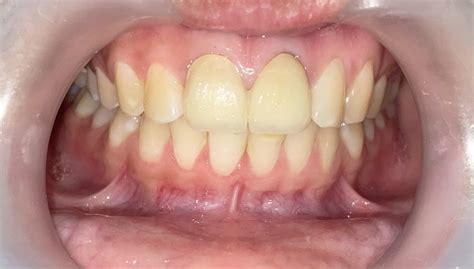

• Darkening or discoloration of the tooth.

5. Restoration: Because a tooth that has undergone an Rct of teeth may become brittle, a crown or permanent filling is usually placed to protect it and restore its original functionality.

Following an Rct of teeth, your tooth may feel slightly sensitive, but this should subside within a few days. You can usually manage this with over-the-counter pain medication as recommended by your dentist. It is crucial to maintain excellent oral hygiene habits—brushing twice a day and flossing daily—to prevent reinfection. While a treated tooth can technically last a lifetime with proper care, regular check-ups are essential to ensure the seal remains intact and the surrounding bone remains healthy.